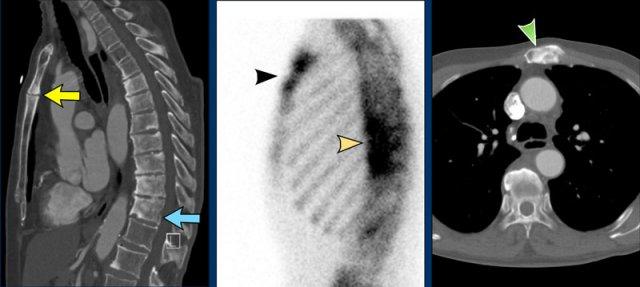

Bệnh nhân mắc hội chứng SAPHO với:

- Viêm xương thân xương ức và cán xương ức, các thân đốt sống ngực xơ hóa, một số bào mòn mâm đốt sống và hình thành cầu xương cạnh cột sống (trái, CT mặt phẳng đứng dọc)

- Tăng chu chuyển xương (giữa, xạ hình xương)

- Xơ hóa tại cán xương ức (phải, CT mặt phẳng ngang)